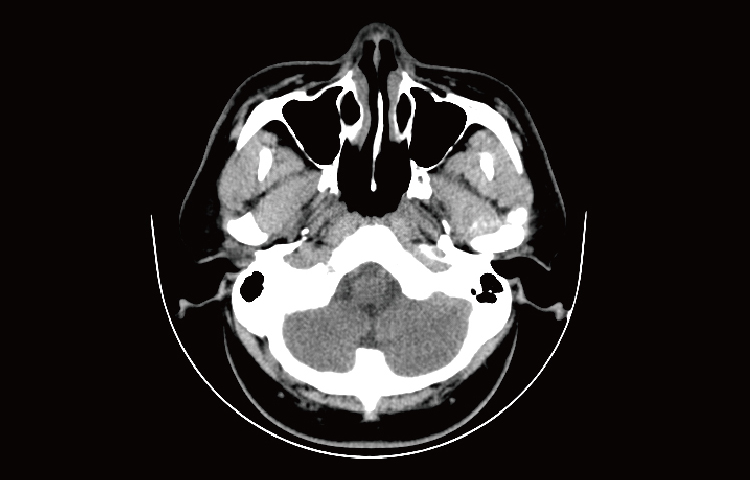

Скриншоты снимков